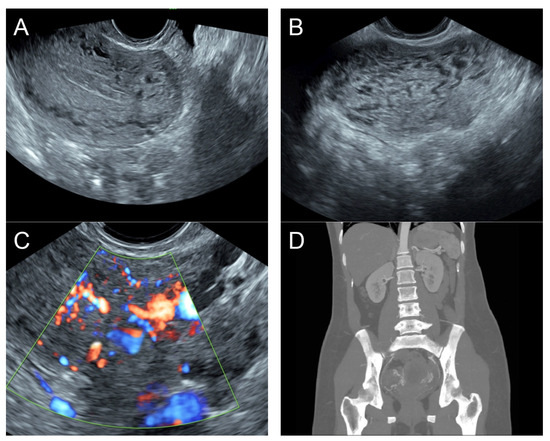

(A) Transvaginal ultrasound: sagittal scan of the uterus showed several dense small anechoic/hypoechoic tubular structures, mainly running to the endometrium, scattered throughout the anterior wall of the uterus; a thin endometrium; no other specific lesions of the uterus. There was anechoic fluid collection in the uterine cavity. (B) Cross-sectional scan of the fundus showed lesions with poorly defined outlines, containing several dense small anechoic/hypoechoic tubular structures, packed in the anterior wall. (C) Color flow mapping showed hyper-vascular areas in the myometrium, without well-defined lesion borders; multidirectional flow mainly localized at the anterior wall and the fundus. The main differential diagnosis was adenomyosis or gestational trophoblastic disease. (D) Spectral Doppler showed a high peak systolic velocity (~50 cm/s) with a low resistance index of 0.3. Note that in differentiating from adenomyosis, which sometime shows multiple minute anechoic or spongy-like areas but not lacunar lakes or tortuous vessels, adenomyosis is characterized by the absence of flow or minimal flow or by the presence of straight, scattered vessels traversing a hypertrophic myometrium [18,19], typically not containing a high flow peak systolic velocity, as seen in AMV, as mentioned earlier.

Management: Initial therapy included blood transfusion, tranexamic acid administration, oral misoprostol 400 mg every 4 h with 3 doses, and intrauterine tamponade with a Foley catheter balloon, resulting in a significant reduction in bleeding. The tamponade was removed after 24 h of indwelling. Combined low-dose contraceptive pills were used for contraception and the prevention of abnormal uterine bleeding. The patient did not have heavy menstrual bleeding during the three months of follow-up. Note that the diagnosis of this case was exclusively based on the sonographic criteria described earlier, without confirmatory CTA.